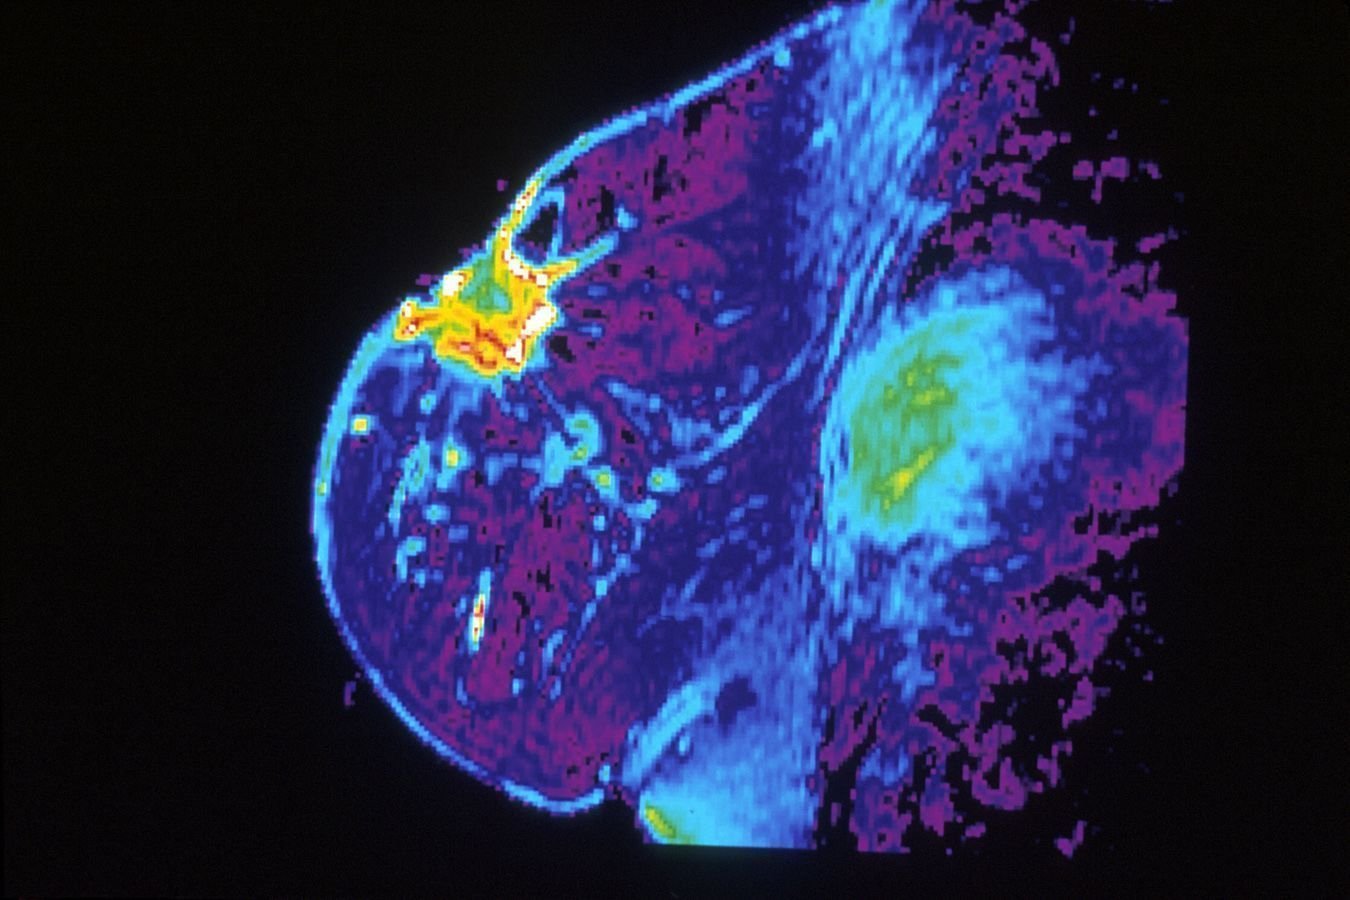

RM de Mamas con Curvas Dinámicas

Evaluación avanzada que analiza el comportamiento vascular de las lesiones en tiempo real, permitiendo una diferenciación precisa entre patologías benignas y malignas con tecnología.